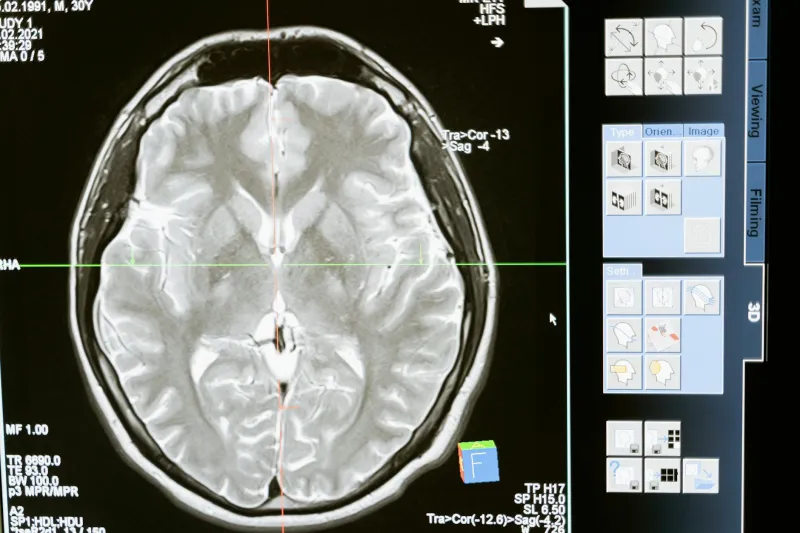

Modern brain imaging technology tells a dramatically different story than the 10% myth suggests. PET scans, fMRI machines, and other neuroimaging tools reveal that even during simple tasks, we're using far more than a tenth of our brain. During sleep — when we're supposedly "inactive" — brain scans light up like Christmas trees.